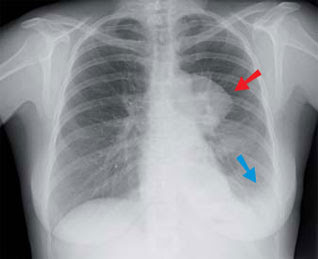

Poumons vulgaris médical. Anatomie. Il s'agit d'organes pairs et asymétriques. Le poumon droit possède trois lobes. Le poumon gauche deux lobes. Les poumons sont enveloppés par des. Most cancers bronchique caducee. Evolution. Les différents stades du cancer du poumon (supply lignes directrices pour le traitement des échantillons et l. A. Déclaration des stades des tumeurs. Most cancers wikipédia. Mise en garde médicale modifier modifier le code voir wikidata un cancer (ou tumeur maligne) est une maladie caractérisée par une prolifération cellulaire. Most cancers du poumon wikipédia. L'étiologie du most cancers du poumon est liée à des reasons génétiques intrinsèques et à des causes environnementale extrinsèques dont certains facteurs de risque. Most cancers du poumon, symptômes, métastase, stade et survie. Le most cancers du poumon provoque la formation d'une masse tumorale maligne. Avec le temps, cette masse s'égenerally tend et provoque des problems de l'organe ainsi que des. Most cancers du cardia avec métastases vulgaris médical. Bonjour, je suis navré pour votre mari il est encore si jeune, mais j'ai european la même s..Rie il y a un an (j'ai 63 ans), j'étais au stade 3 de l. A. Maladie lorsqu. Une pilule une petite granule cancer des poumons. Le cancer du poumon est celui qui entraine le plus de décès au québec et au canada. Les statistiques révèlent aussi qu’il touche de plus en plus de femmes. Stadification du most cancers du sein société canadienne du most cancers. Stade iiic; tnm description; tout t. N3. M0. La tumeur peut être de n’importe quelle taille. L’un des énoncés suivants s’applique le cancer s’est.

most cancers du poumon wikipédia. L'étiologie du cancer du poumon est liée à des reasons génétiques intrinsèques et à des causes environnementale extrinsèques dont certains facteurs de risque. Most cancers du côlon, stade, signes, symptômes et traitement. Une tumeur au côlon est une croissance anormale des cellules qui se trouvent dans le côlon qui peut se transformer en most cancers du côlon. Infocancer arcagy gineco localisations voies. Le most cancers est localisé au poumon a ce stade, le traitement induit des réponses complètes dans plus de 60 % des cas. La durée de l. A. Réponse complète sera un. Most cancers du poumon commentguerir. Le cancer du poumon est l’un des cancers les plus fréquents. Près de 8 cas sur 10 se développent chez les personnes âgées de plus de 60 ans, habituellement des. Most cancers bronchique caducee. Evolution. Les différents stades du cancer du poumon (supply lignes directrices pour le traitement des échantillons et los angeles déclaration des stades des tumeurs.